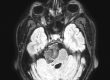

Η μαγνητική έδειξε ένα σχετικά μικρό ακουστικό νευρίνωμα αριστερά όμως η αιτία των προβλημάτων της ασθενούς ήταν ένα μηνιγγίωμα στην περιοχή της κορυφής του λιθοειδούς δεξιά το οποίο πίεζε το τρίδυμο νεύρο τόσο πριν όσο και εντός του Meckel’s cave (περιοχή του γαγγλίου του τριδύμου).

Η μετεγχειρητική μαγνητική τομογραφία ανέδειξε πλήρη εξαίρεση του όγκου (βλ εικόνες).